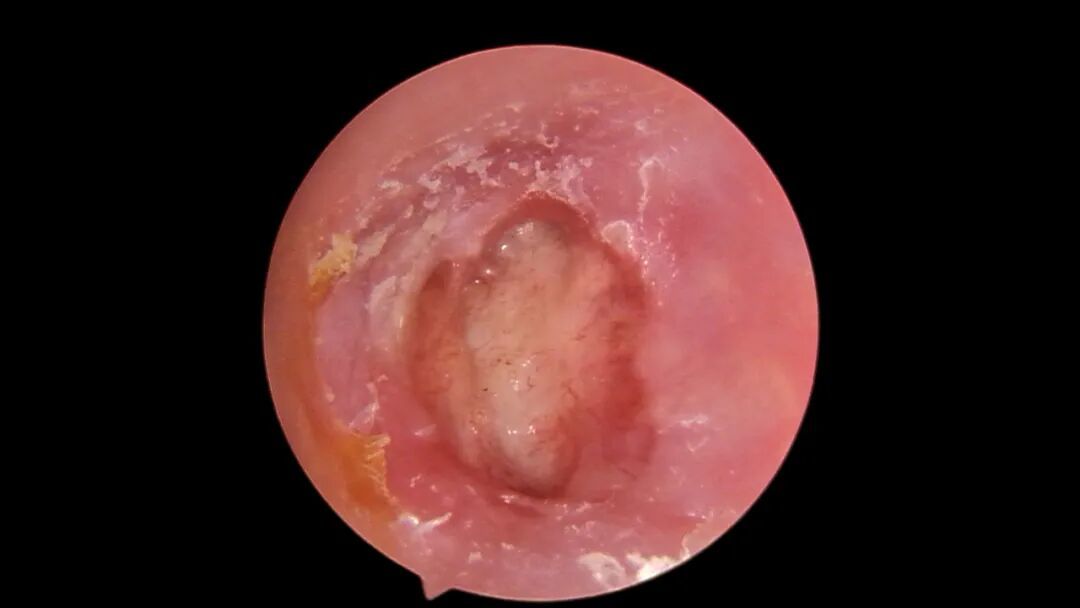

术后鼓膜完整

术后,即便耳道内仍有填塞物,刘大爷也感听力明显改善,且无明显疼痛不适。经过精心护理,恢复情况良好。术后三个月复查显示,其左耳听力不仅显著提升,甚至优于右侧健康耳朵。长达二十年的流脓困扰彻底消失,听力恢复正常,老人脸上露出了久违的笑容,并专程赠送锦旗以表感激之情。

左耳术后照片